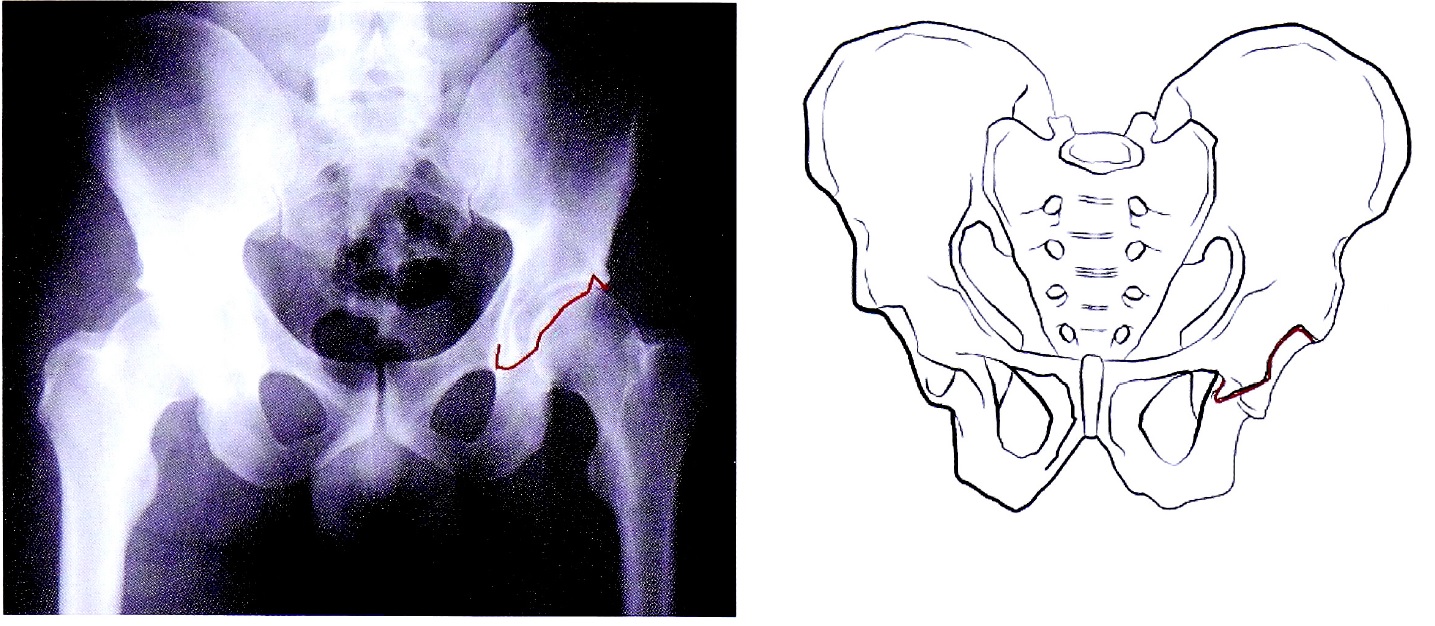

- Подвздошно-гребешковая линия (соответствует терминальной линии тазового кольца) в передних отделах соответствует передней колонне вертлужной впадины, в задних отделах она отражает тело подвздошной кости на протяжении до крестца — в норме она непрерывна (рис. 1). С клинической точки зрения целостность тазового кольца определяет непрерывность подвздошно-гребешковой линии.

Рис. 1. Подвздошно-гребешковая линия на рентгенограмме и на схематическом изображении таза.

Fig. 1. Ileopectineal line on AP pelvic X-ray and on schematic pelvis.